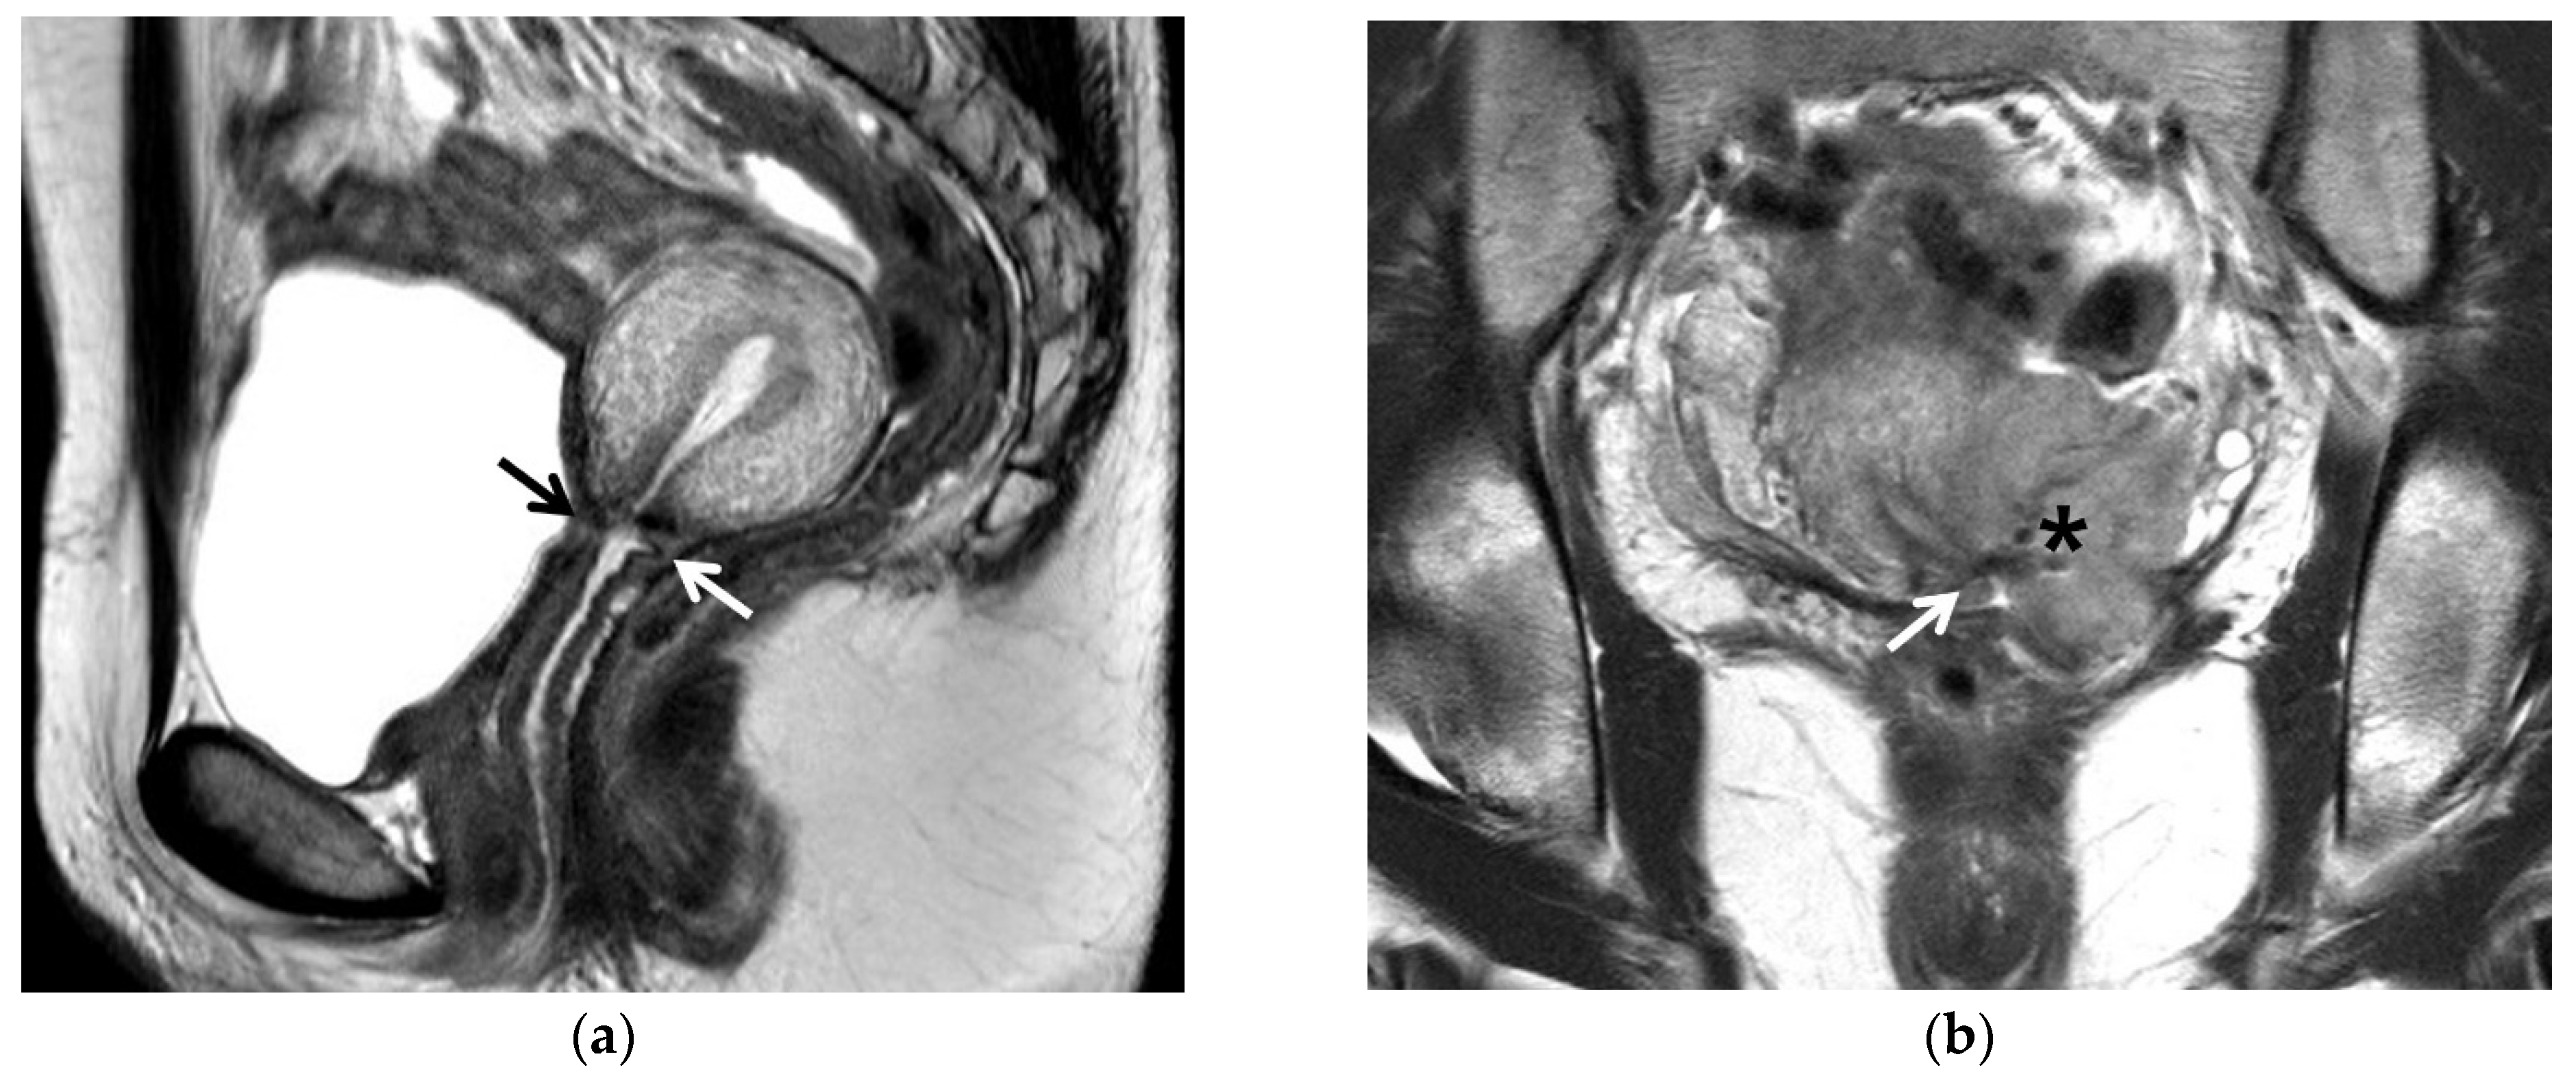

5. Post-Trachelectomy MRI

6. MRI for Endocervical Cancer